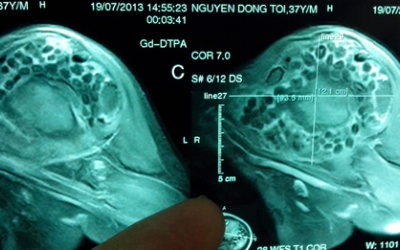

Các bác sĩ Trung Quốc vừa phát hiện một thai nhi không phát triển trong dạ dày bé trai 4 tuổi có phần bụng phình từ lúc mới sinh ra, tờ Star dẫn nguồn báo Kwong Wah Yit Poh đưa tin.